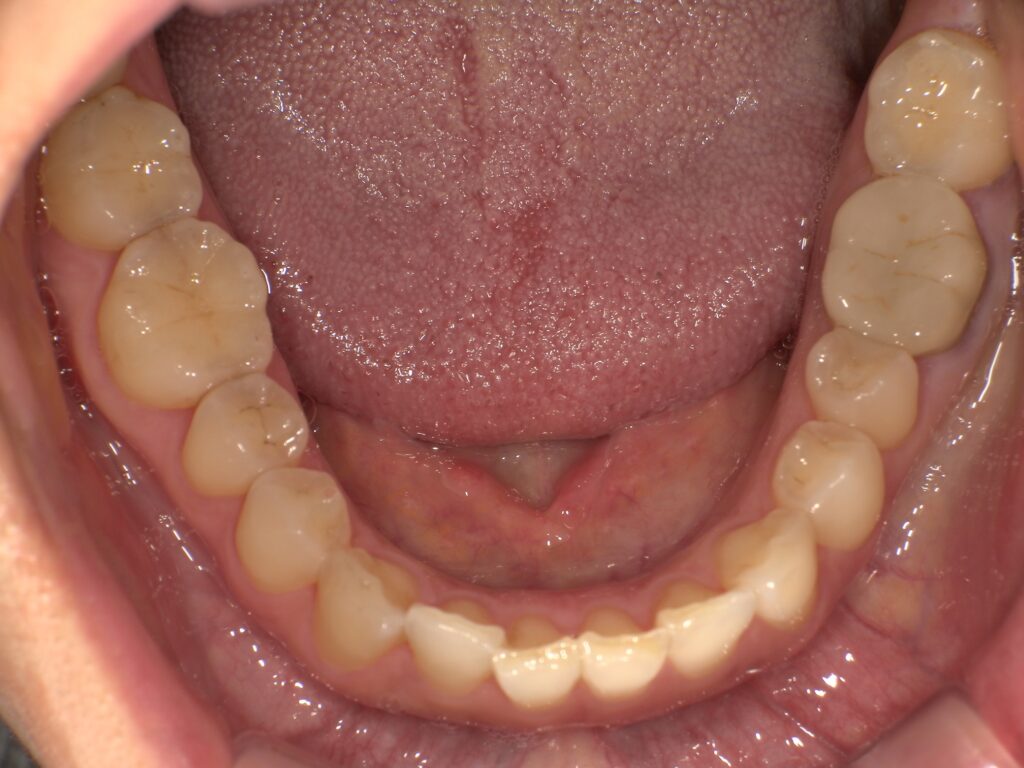

治療後、審美面にご満足いただき、「他の金属の部分もセラミックに変えたい」とのご希望があったため、順次やり替えていくことになりました。まずは、お口を開けた際に目立ちやすい下顎から治療を進めています。

そして、右上5番の歯については、金属の詰め物を除去し、保険診療で対応可能な白い詰め物(CR)で修復しました。

【治療前】

【治療後】